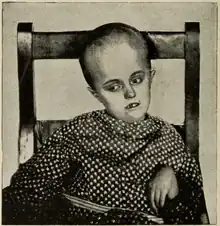

| An MRI of a patient with benign familial macrocephaly (male with head circumference > 60 cm) | |